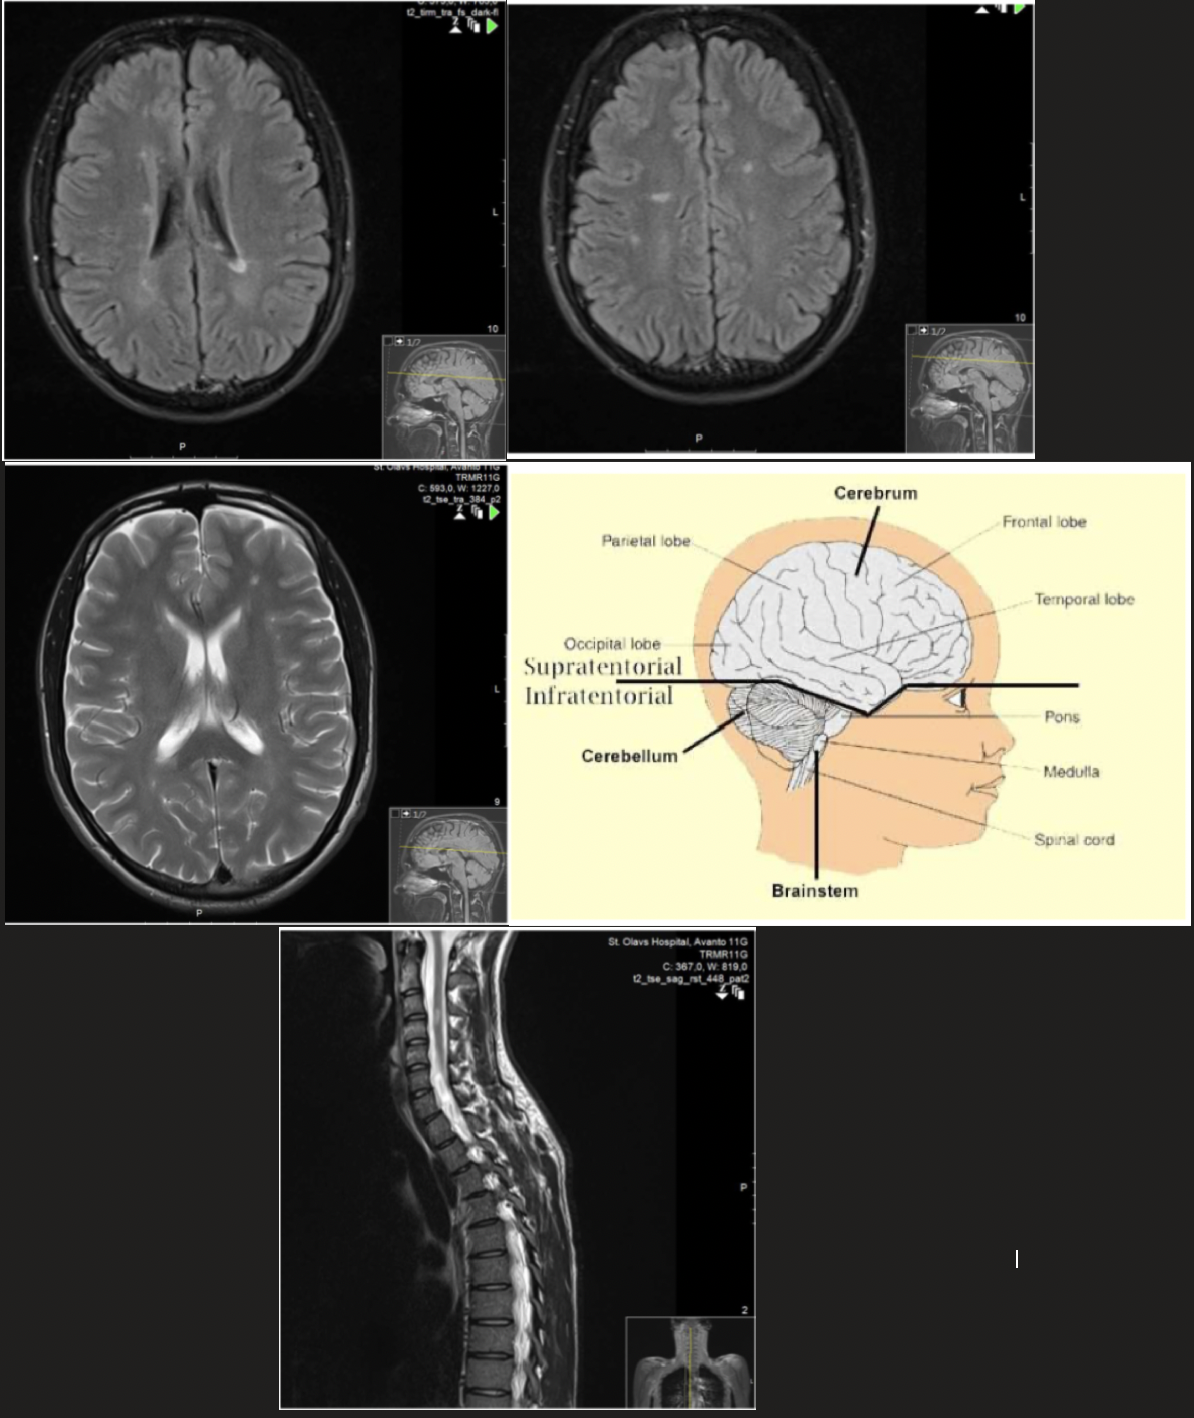

Hvilken bildediagnostisk undersøkelse er viktig ved utredning med mistanke om MS?

Hvilke funn sannsynliggjør en diagnose?

MR caput og medulla spinalis

- Tar MR av nevroaksen, med kontrast

- Akutte plakk (lesjoner) lader kontrast som oftest i 2-3 uker

MR-lesjoner lokalisert:

- Periventrikulært

- Juxtakortikalt (subkortikalt) eller kortikalt

- Infratentorielt

- Ryggmarg